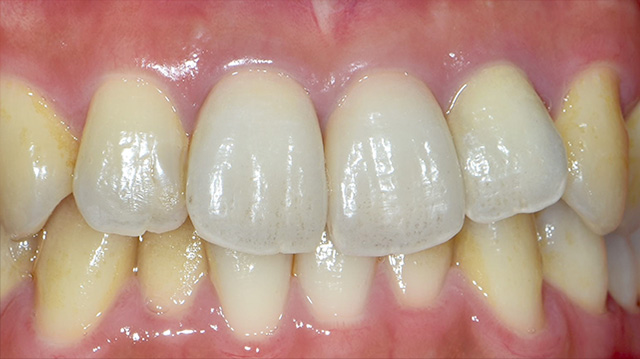

| 年代・性別 | 50代 男性 |

|---|---|

| 主訴 | 前歯を綺麗にしたい |

| 治療回数 | 3回 |

| 治療期間 | 約1ヶ月 |

| 費用 | 仮歯 5,500円 ジルコニアクラウン 176,000円 |

*キャンセルポリシーをご一読のうえご予約ください